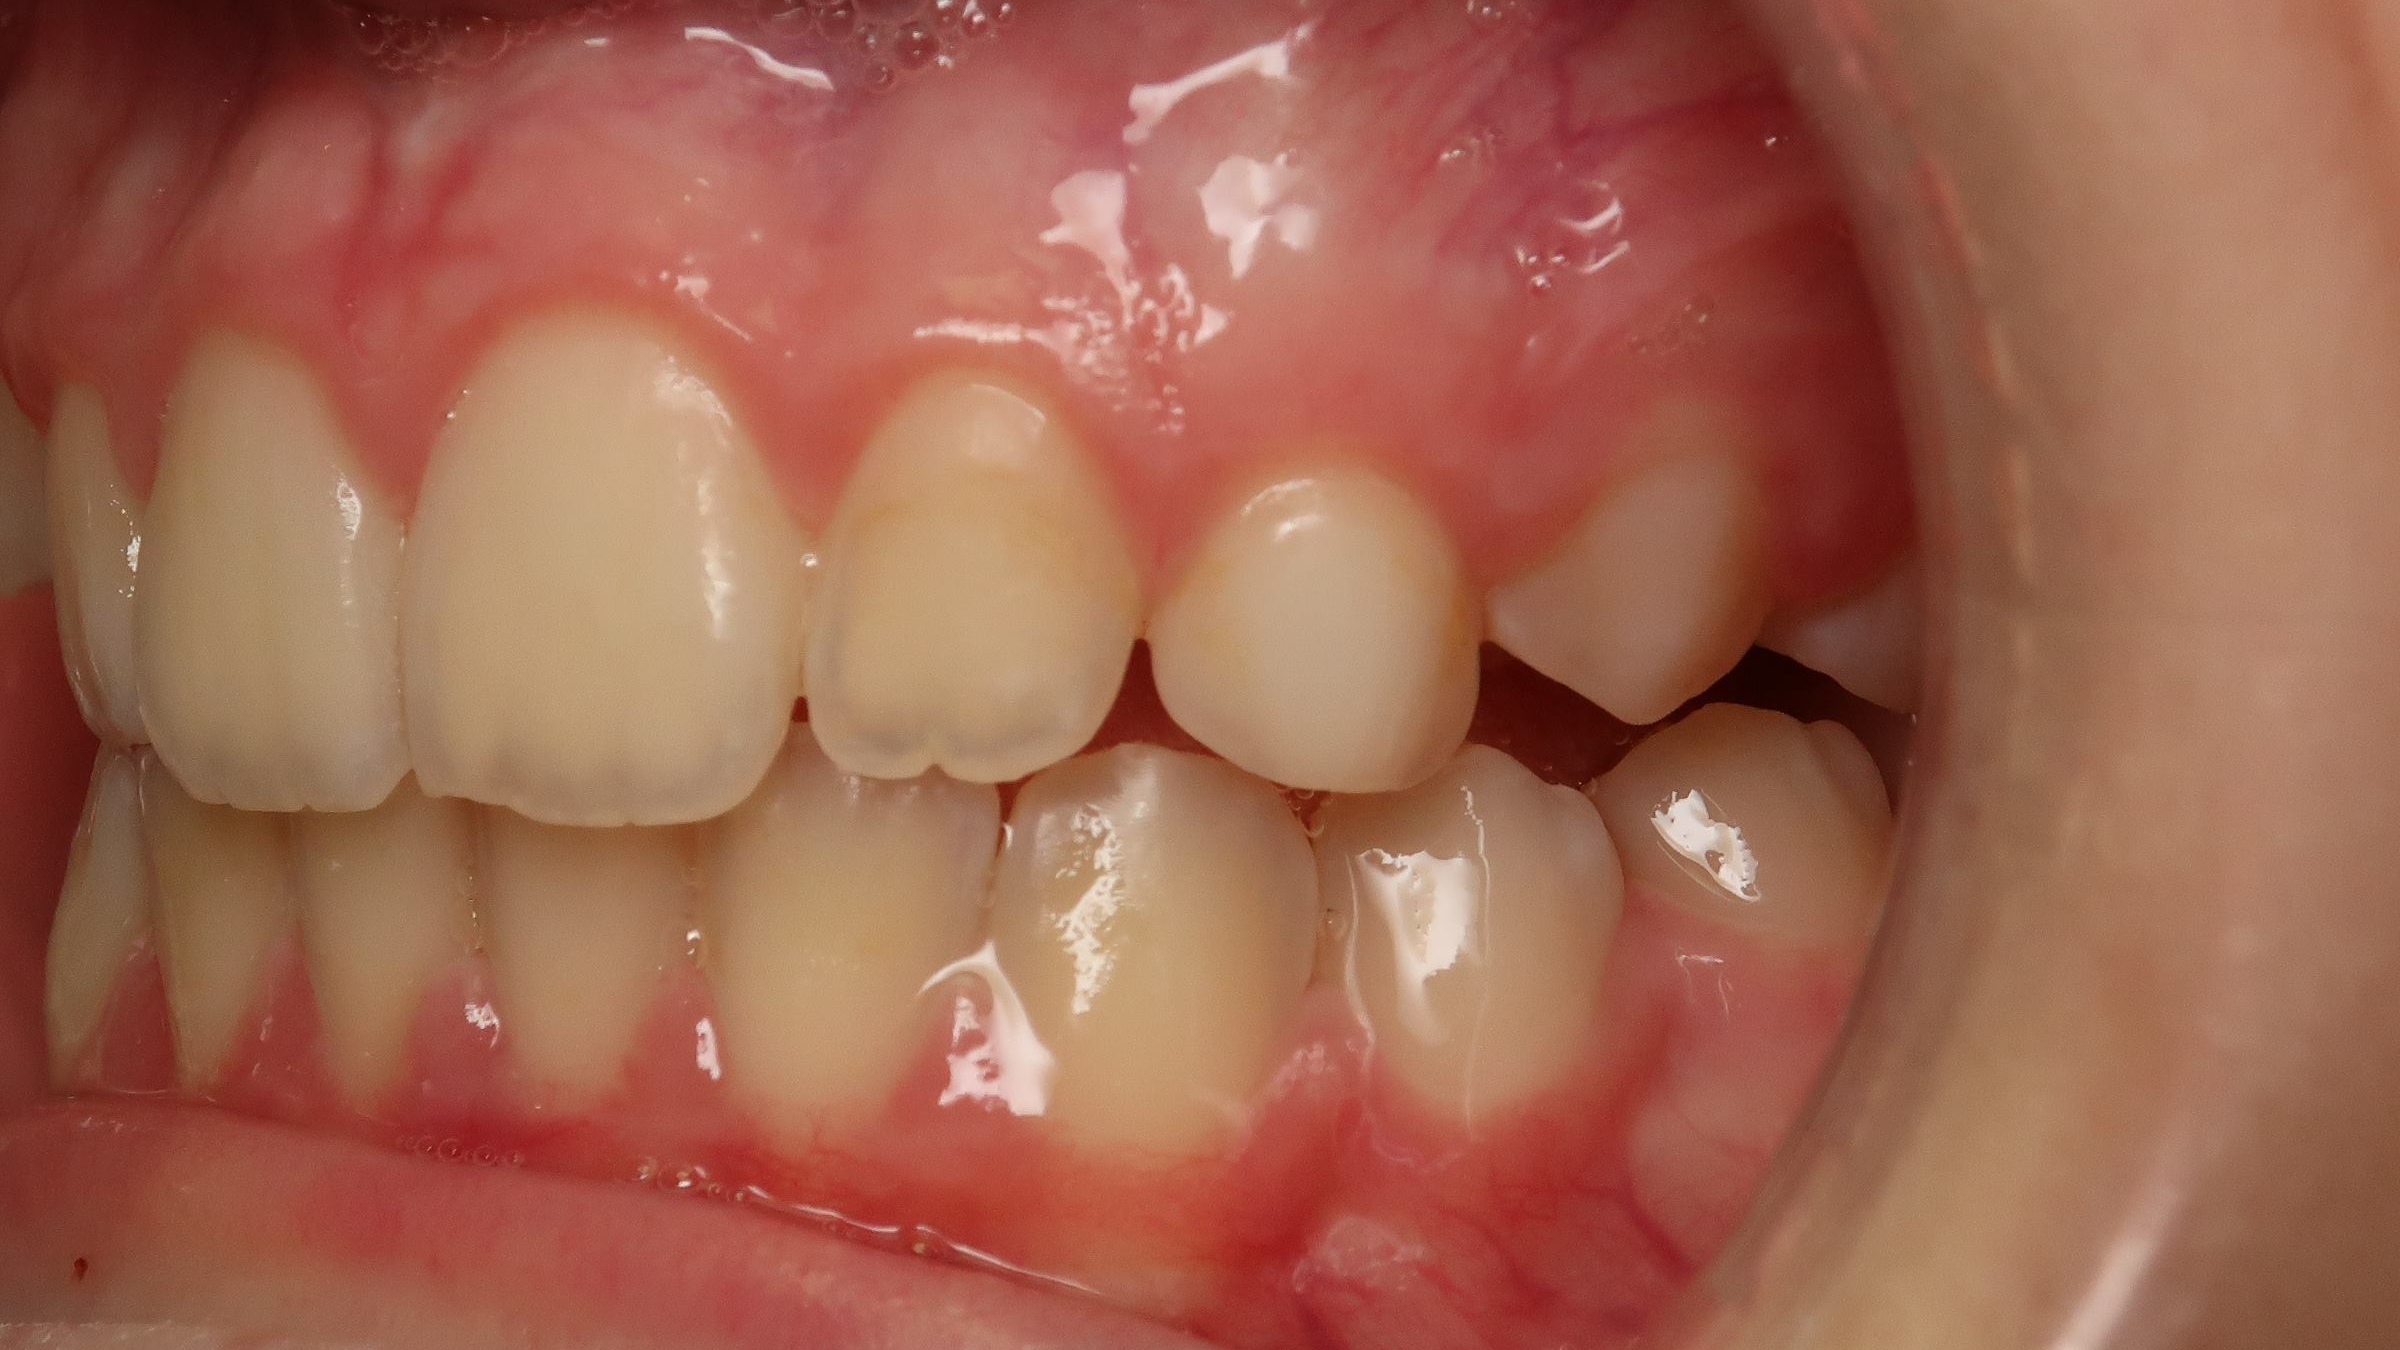

18 béance inversé droit 4 ans

inversion des dents postérieur et espace entre l'arcade du haut et du bas (béance)

bilan de début et en cours de traitement